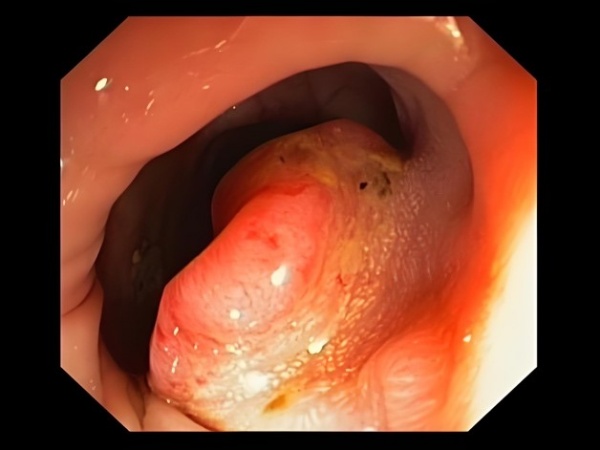

1.肠镜检查(金标准)

医生用一根带摄像头的软管从肛门进入肠道,直接查看肠壁上是否有息肉或可疑肿块。

当发现可疑组织病变可以当场夹取米粒大的组织进行活检(病理学检查)。

如果有些人害怕疼痛不适,还可以选择无痛肠镜:打一针麻药,睡一觉就做完,怕疼的人不用慌!

(肠癌在肠镜下的表现)